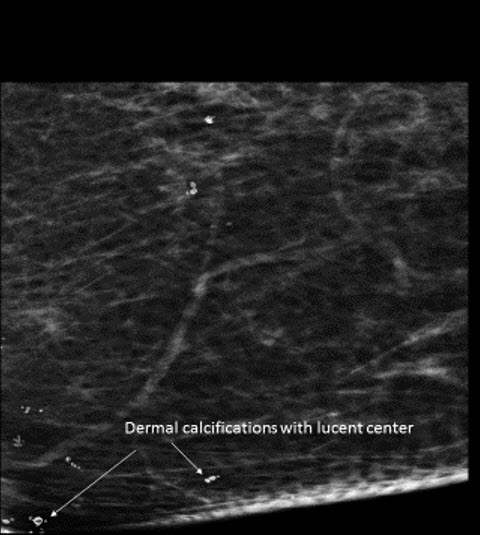

Calcifications

There are calcifications. [Yes/No]

The calcifications are benign (vascular, coarse dystrophic, secretory, skin, milk of calcium). [Yes/No]